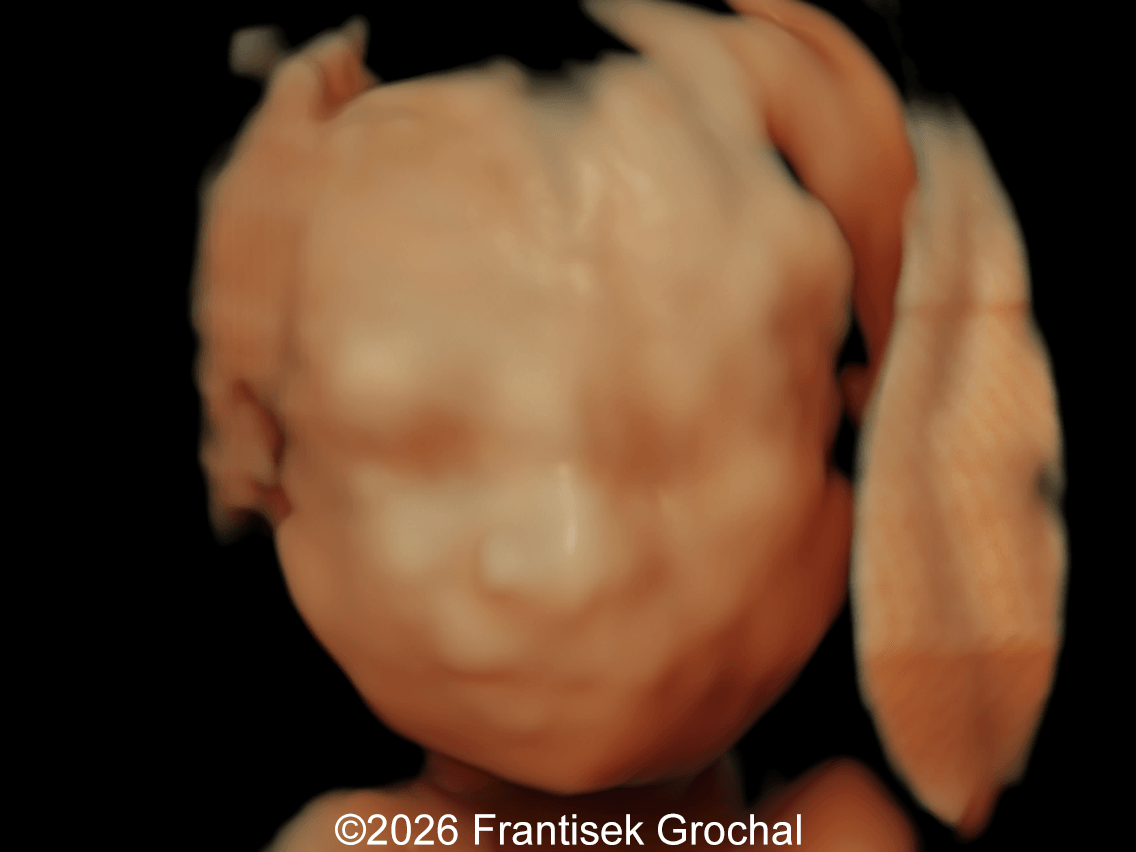

There is broad consensus that the postnatal diagnosis of Wolf-Hirschhorn syndrome relies on the association of characteristic facial dysmorphism (prominent forehead, hypertelorism, and wide nasal bridge continuing to the forehead, known as “Greek warrior helmet appearance”), growth retardation, intellectual disability, and seizures or electroencephalographic abnormalities [8]. Zollino et al [8] suggested classification of the syndrome based on the size of the deletion: “mild” (deletions < 3.5 Mb), “classical” (deletions 5–18 Mb), and “severe” forms (deletions > 22–25 Mb).

Most prenatally diagnosed cases show growth restriction, microcephaly, and characteristic craniofacial appearance. The severe early‑onset growth restriction is present in nearly all affected fetuses [11,12] and marked microcephaly persists after birth [13]. The characteristic craniofacial appearance is defined by a prominent glabella, wide nasal bridge with a beaked nose, high forehead, hypertelorism, downturned corners of the mouth, and a short philtrum [14-16]. Based on combined pre‑ and postnatal data, the ultrasound phenotype can be grouped according to its frequency [Table 1] [1]:

15. Sepulveda W. Prenatal 3-dimensional sonographic depiction of the Wolf-Hirschhorn phenotype: the "Greek warrior helmet" and "tulip" signs. J Ultrasound Med. 2007 Mar;26(3):407-410.